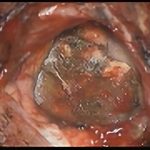

症例 '16年12月

No.

’16_178

'16年12月

50代

脳腫瘍

術中写真

摘出 前

摘出 中

摘出 後